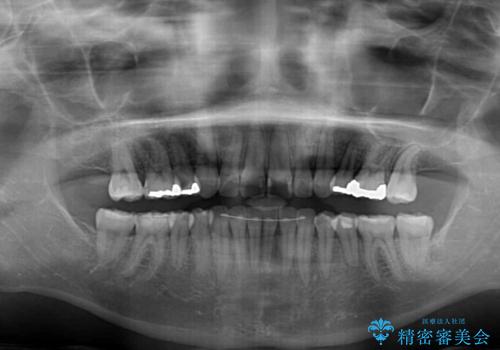

- 上の前歯の捻じれと突出感を気にして来院された患者様です。

目立たない装置を希望とのことで、上顎左右第一小臼歯を抜歯し、インビザラインにて矯正治療を行うこととしました。

インビザラインにて抜歯矯正を行うと、高頻度で奥歯が咬み合わなくなります。

抜歯スペースが閉じてからも咬みにくさ改善のためマウスピース矯正を継続するため、治療期間は長期化します。